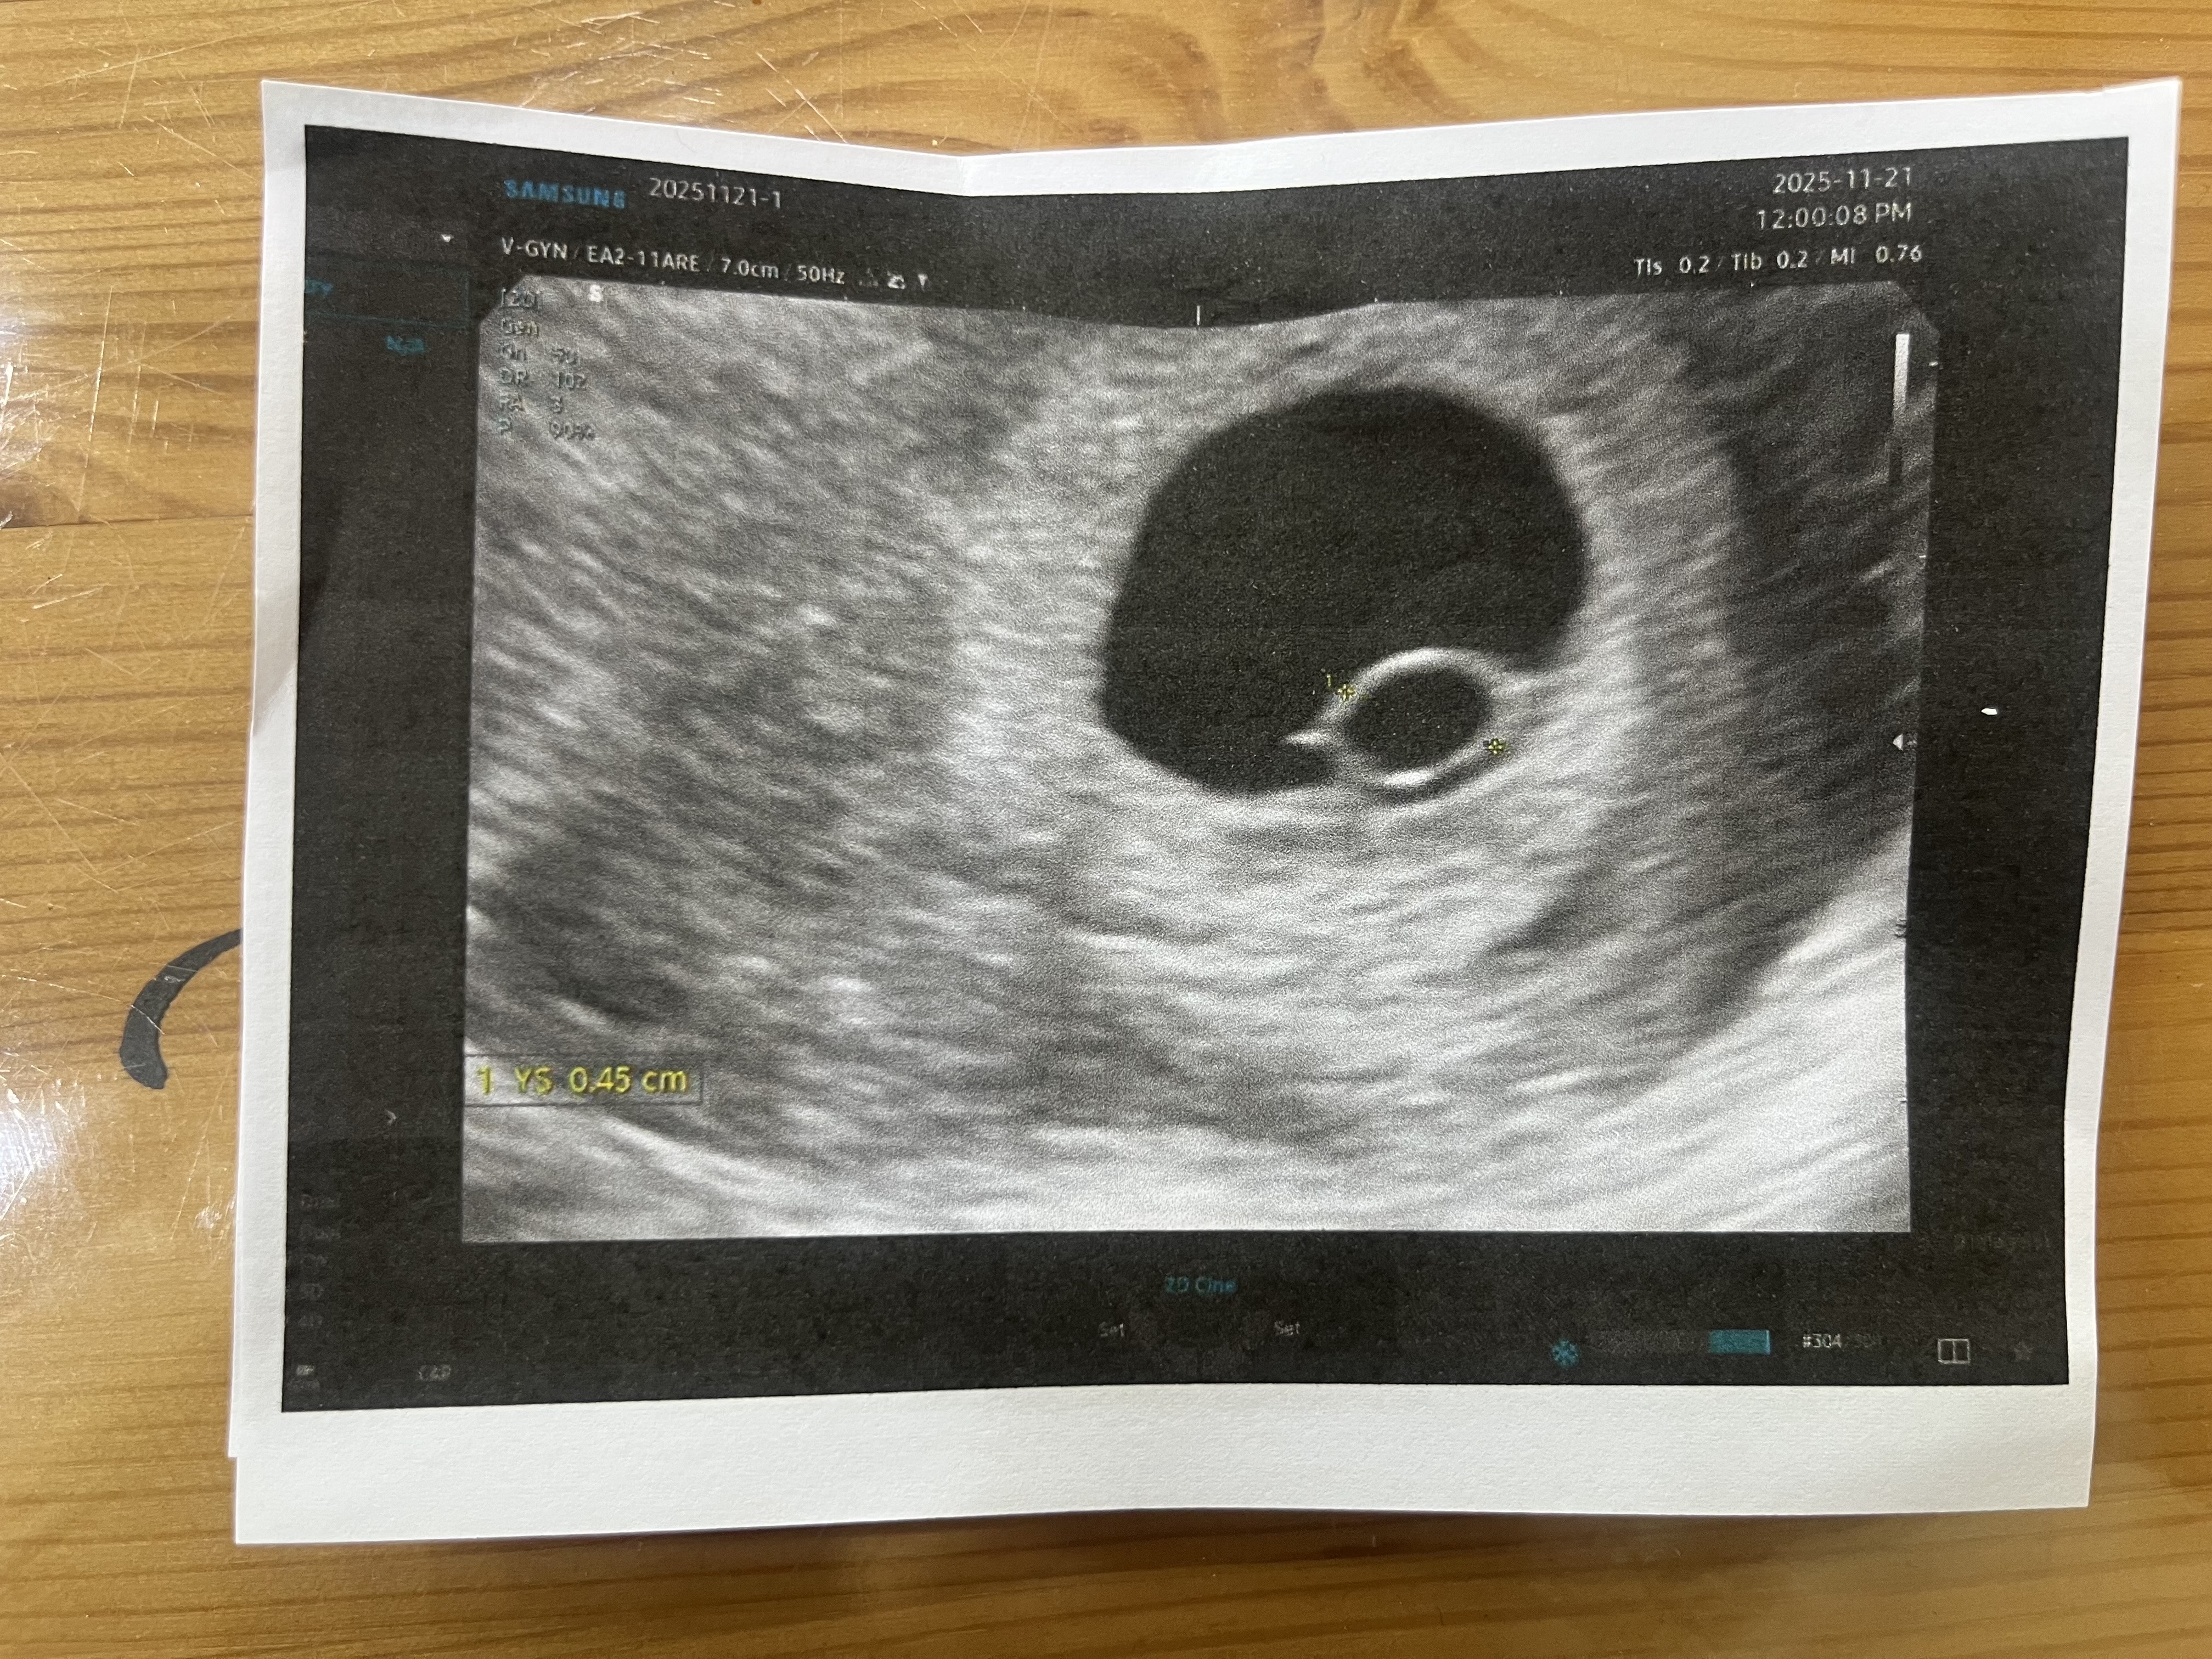

난황은 있고 배아가 안 보인대요

막생 기준 7주4일인데, 난황은 생기고 배아는 없다고 하네요. 담주에 다시 오라는데 다들 배아 언제 생기셨어요 ㅠ